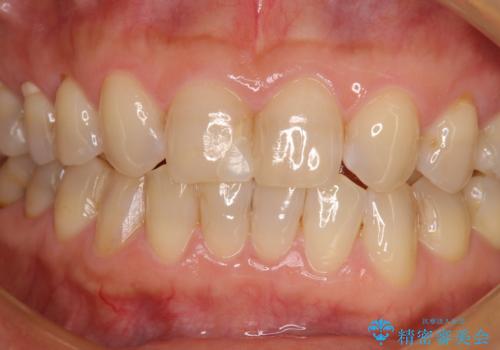

- 上顎2前歯の色を気にして来院された患者様です。

2本ともに虫歯治療による充填材の変色などによりつぎはぎのような前歯となっていたため、オールセラミッククラウンにて補綴治療を行うこととしました。

今後ホワイトニングをする予定とのことで、少し明るめのトーンに仕上げました。